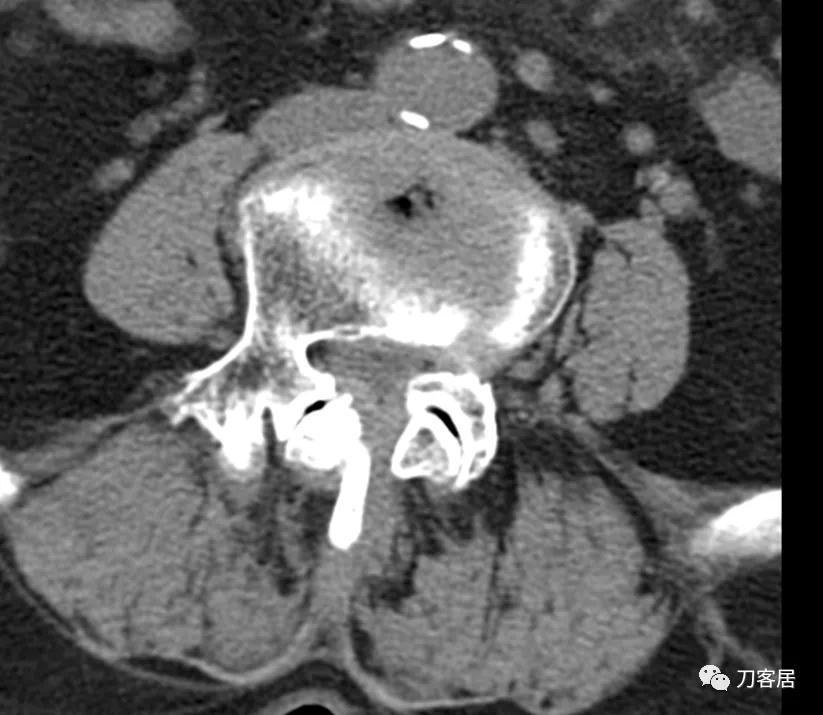

@胡满 如果是我的话,对于这种病例,首先抗骨质疏松治疗半年后再看情况,而且如果患者经济条件可以的话,建议直接使用特立帕肽,因为从患者的X线片来看,骨质疏松严重。患者的腰5滑脱应该是真性滑脱,腰5有峡部裂,腰4滑脱是退变滑脱,腰4-骶1椎管狭窄。但患者的痛苦不一定是椎管狭窄引起的。即使是做手术,患者的骨密度太低,钉子把持力不够。所以,先正规抗骨质疏松半年后再说手术吧。

患者为69岁,女性, 就诊日期:2021年11月8日。因晨起腰痛2天,就诊当日有缓解。疼痛自腰部放射至大腿后侧。2004-2005年曾有腰椎骨折病史,保守治疗后愈。

腰椎X线片提示腰5峡部裂,腰5椎体前滑脱1度,膝关节X线片提示退变增生,右侧髌股关节增生、狭窄、骨刺形成。骨密度提示骨质疏松,T值最低-3.3。2014年曾换心脏瓣膜手术,长期服用华法林,辅酶Q10, 盐酸曲美他嗪。

诊断:骨质疏松症,腰5峡部裂,腰5椎体前滑脱1度,双膝关节创伤性关节炎。